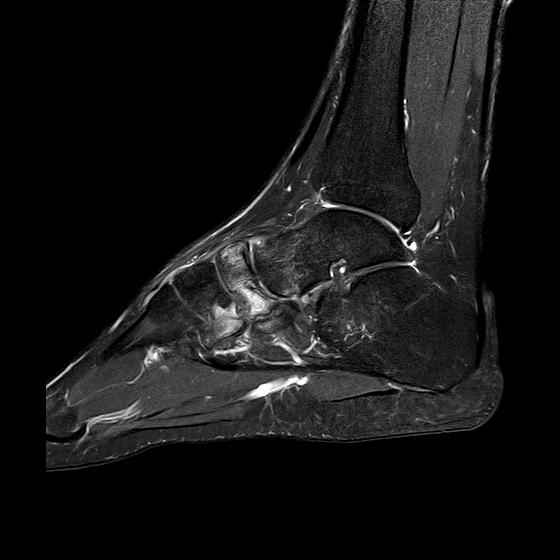

Мужчина 36 лет, пострадал около 8 месяцев назад в ДТП (водитель мотоцикла).

Подтаранный вывих лечили гипсовой лонгетой. Недиагностированным остался перелом ладьевидной кости, который беспокоит в настоящее время. Аваскулярный некроз кости, похоже.